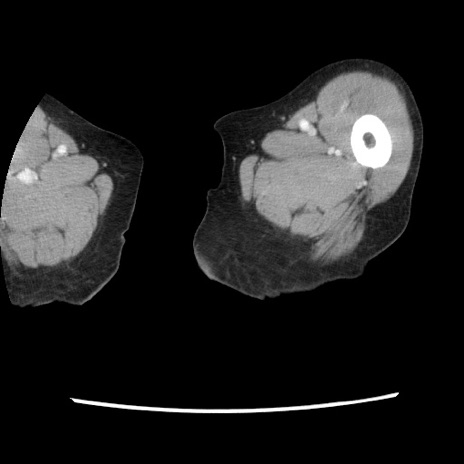

症例1(横断像)

【症例】80歳代女性

【主訴】腹痛

【現病歴】8時間前から腹痛あり来院。

【既往歴】糖尿病、脂質異常症、子宮体癌にて子宮全摘術

【身体所見】意識清明・会話良好だが腹痛で苦悶様、全腹部にわたって反跳痛と圧痛あり

【データ】WBC 13600、CRP 0.14、LDH 224、CK 90